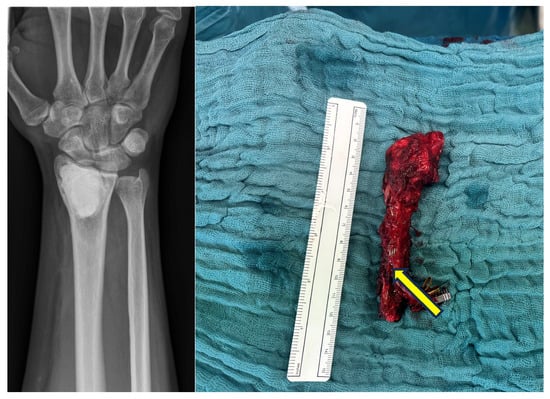

Arthrodesis of the Wrist with Vascularized Fibula Flap for the Treatment of a Large Defect of the Distal Radius

| GROUP 1 | Case 1 | Distal radius, parts of the proximal wrist | Trauma | 6 month | 32 | 9 cm | Vascularized fibula | Wrist arthrodesis | N/A N/A | 0-0-0° 40-0-50° | 60% | MMWS = 50 DASH = 24 | yes |